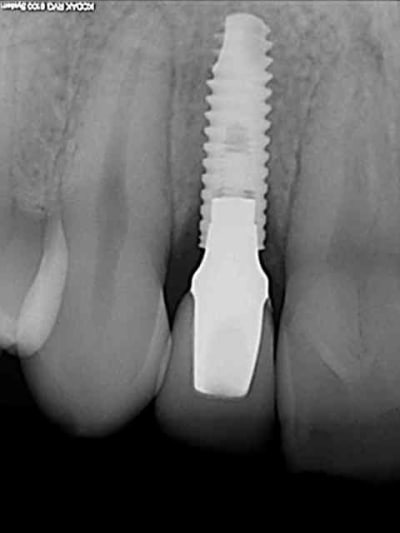

01/09/2010 à 16h54

-1 ou 2 mois plus tard ( je sais plus)

- empreinte avec transfert pop in

- pilier zircone esthétique Axiom

- prothèse et pilier

- pilier zircone en place

- couronne en place (petite compression gingivale)

fin du traitement